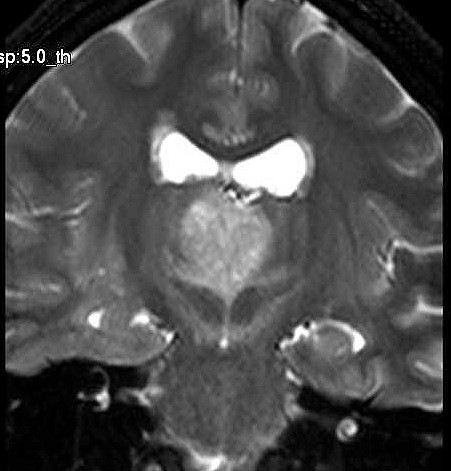

| Fem. 17a. |

| Nódulo sólido homogêneo preenchendo o III ventrículo, com limites precisos, com hipossinal em T1 e hipersinal em T2 e FLAIR, que se impregna por contraste paramagnético. Lesão menor implantada no assoalho do IV ventrículo provavelmente representa disseminação por via liquórica. |

| F. 17a. Tumor teratóide rabdóide atípico de III ventrículo. RM | HE | VIM, GFAP | HHF35, desmina, 1A4 | AE1AE3, EMA |